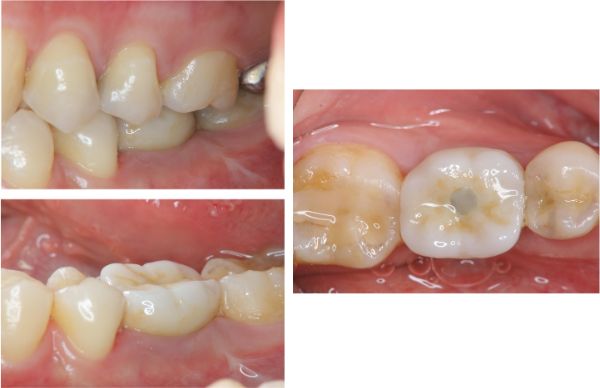

照相比色

固位後口內照

術前、術後比較